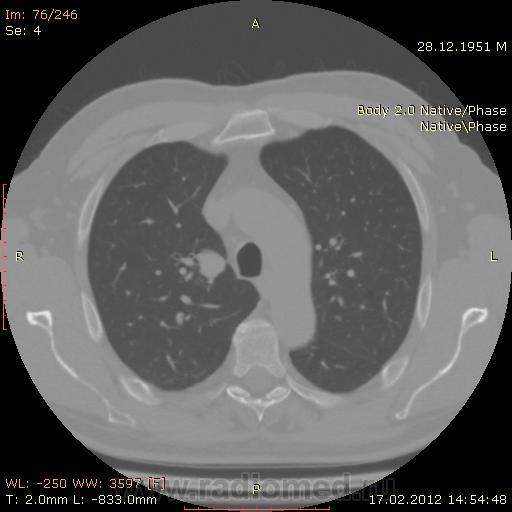

КТ.

В феврале 2012 года при очередном флюрографическом обследовании были обнаружены изменения в лёгких. По собственной инициативе было сделано КТ лёгких.